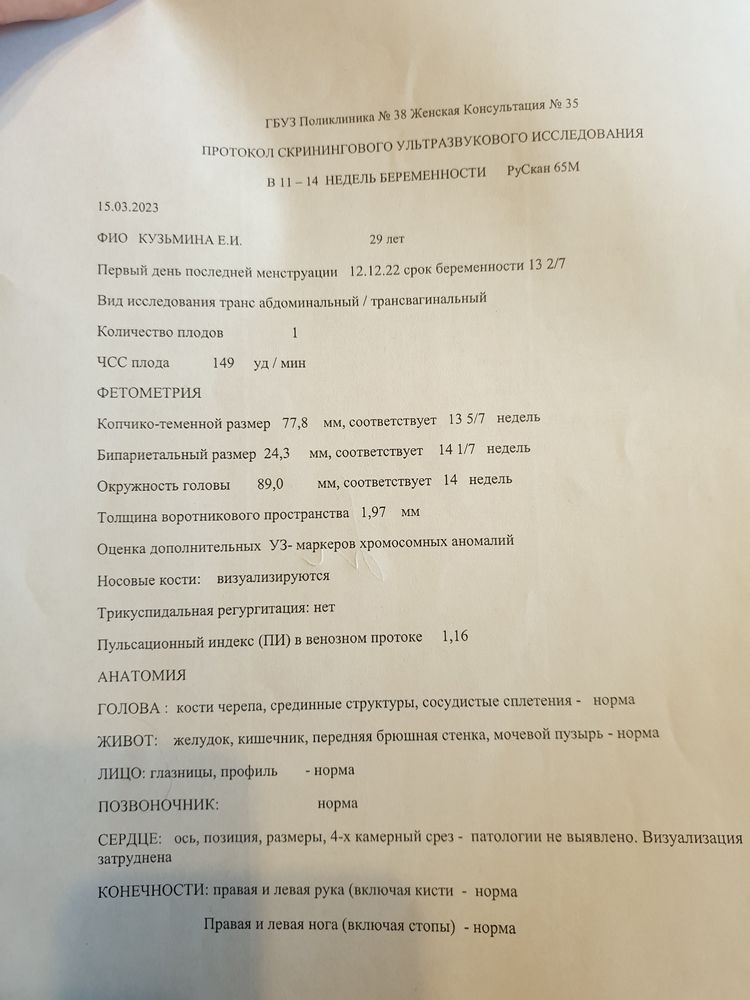

Марина, то было 13 февраля, а это 15 марта

Марина, то было 13 февраля, а это 15 марта